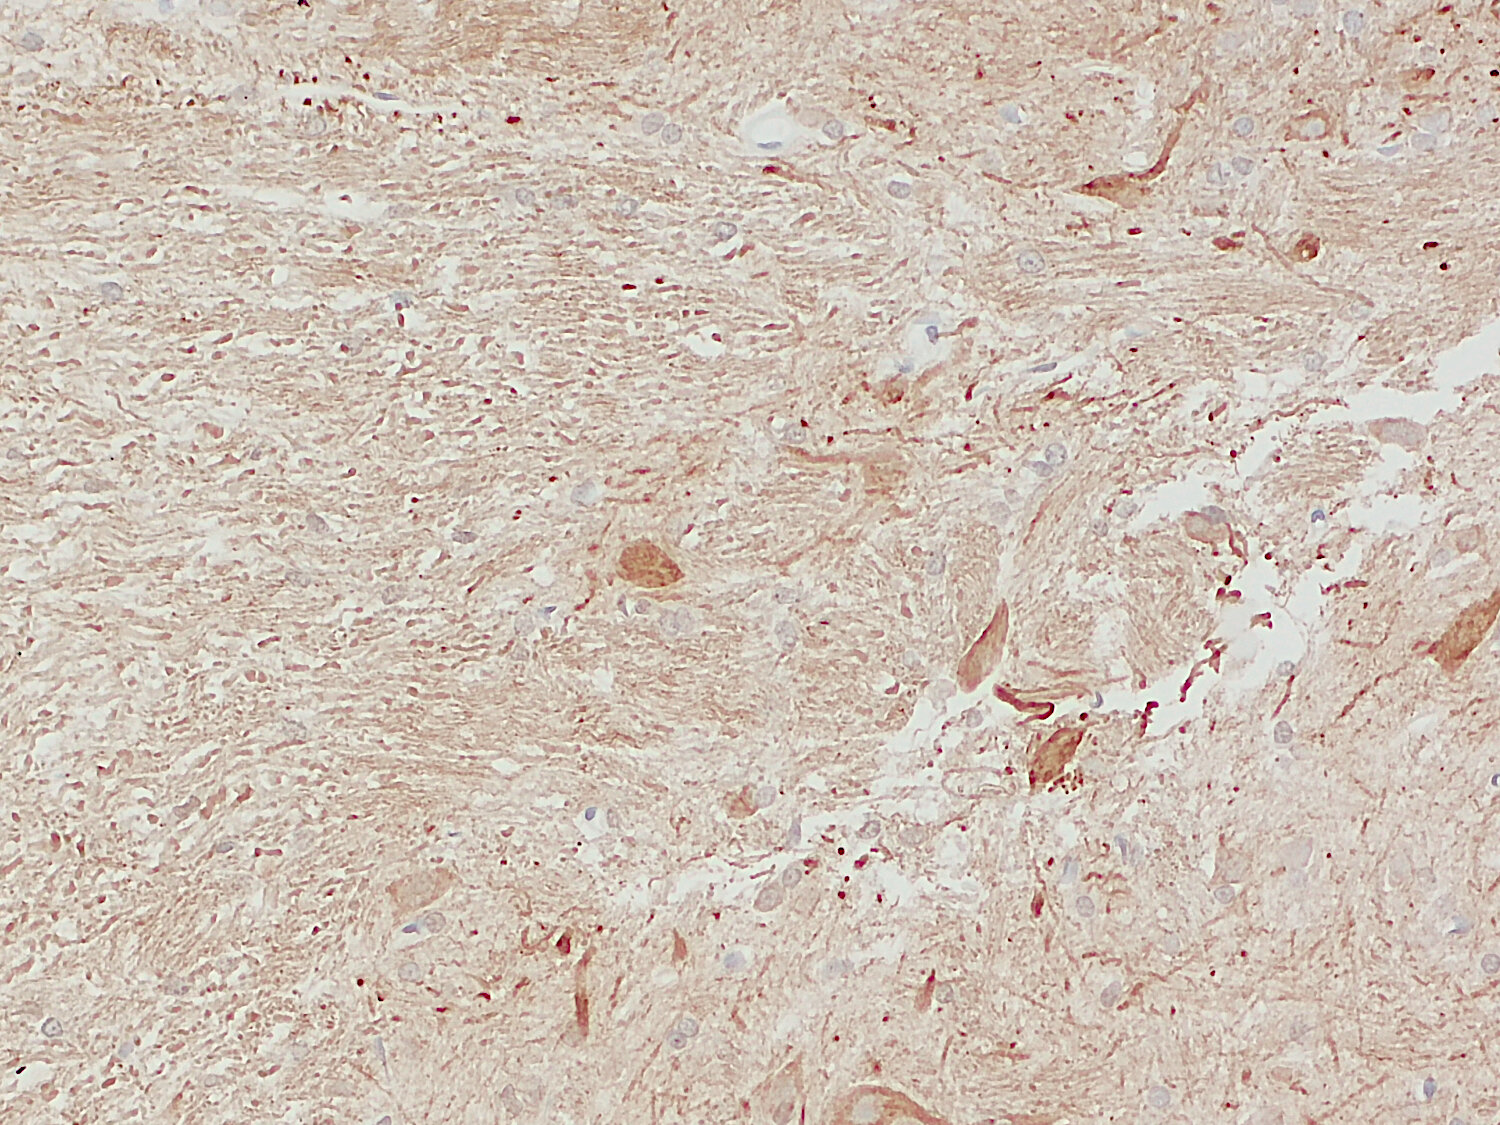

IHC-P: 1 : 100 up to 1 : 1000 gallery

Immunohistochemistry (IHC-P) of formalin fixed, paraffin embedded (FFPE) tissue (some antibodies require special antigen retrieval steps, please refer to the ”Remarks” section). Immunoreactivity is usually revealed by fluorescence or a chromogenic substrate.